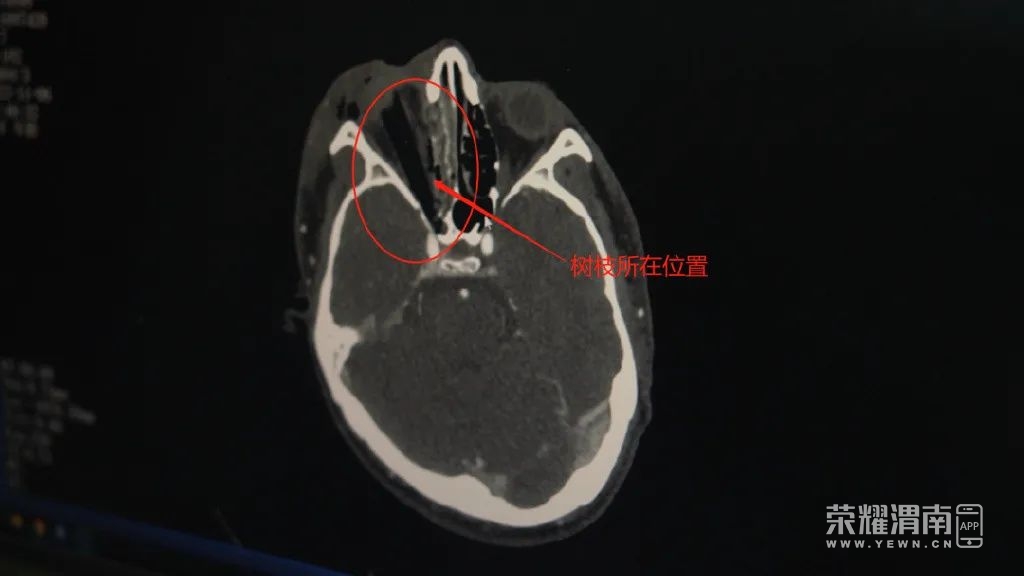

考虑到树枝插入比较深,离海绵窦及颈内动脉较近,不是单纯拔出异物那么简单。在手术过程中,很可能损伤颅内血管导致大出血危及患者生命,需要联合神经外科共同完成手术救治患者。

西安市人民医院(西安市第四医院)脑科病院院长 刘卫平:“树枝已经扎到颈内动脉压计,这个位置有些地方是有一层薄薄的骨头,有些可能没有骨头,所以非常危险,如果一旦血管刺破或者拔的时候血管有破损,血就会像自来水龙头一样,一下子把整个鼻腔填的满满的。”

102241uqpjcj6vtdcezs26.png

西安市人民医院(西安市第四医院)眼部急症与眼外伤病院副主任 朱昭亮:“所以这个树枝扎进去以后,我们就不能轻易随便拔出,必须要相关科室,比如脑外科把伤口暴露以后,把棍子的尖端和颈内动脉关系搞清楚后,我们才能从外面把它拔出来。”

眼部急症与眼外伤病院院长宋虎平团队和脑科病院院长刘卫平团队根据异物部位和脑血管关系,共同拟定了周密的手术计划,切开蝶窦组织,发现树枝、树皮等异物后,在内镜监测下拔除插入眼眶的树枝。

经过两个小时的紧张手术,在多科室的共同努力下,完整取出了田先生眼眶内的1.5厘米粗,近6厘米长的树枝。